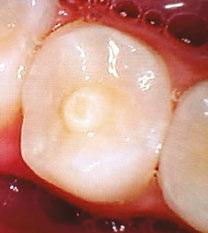

Figure 3 (left): Preoperative CBCT scan of tooth No. 20 showing evidence of a wide open apex. Figure 4 (right): Bleeding noted in the canal immediately after removing the GentleWave platform

In this case report, we present a 10-year-old patient with a wide open apex and a dens evaginatus.5 This case was successfully managed with single visit regenerative endodontics using the GentleWave® System (Sonendo®).6 The outcomes demonstrate not only the feasibility but also the efficacy of this approach in achieving favorable clinical and radiographic results in pediatric patients.

A 10-year-old female patient with a history of swelling and pain associated with tooth No. 20 was referred to our office. The patient exhibited severe dental anxiety. Upon clinical evaluation, a dens evaginatus was noted on the occlusal surface of the tooth (Figure 1). The tooth was sensitive to percussion, palpation, and bite stick while cold testing yielded no response. A periapical radiograph and CBCT scan (Carestream 9600) revealed a wide open apex and evidence of apical periodontitis, leading to the

Figure 1 (left): Dens evaginatus noted on the occlusal surface. Figure 2 (right): Preoperative periapical radiograph of tooth No. 20 showing evidence of apical periodontitis and a wide open apex

diagnosis of a necrotic pulp and symptomatic apical periodontitis of tooth No. 20 (Figures 2 and 3).